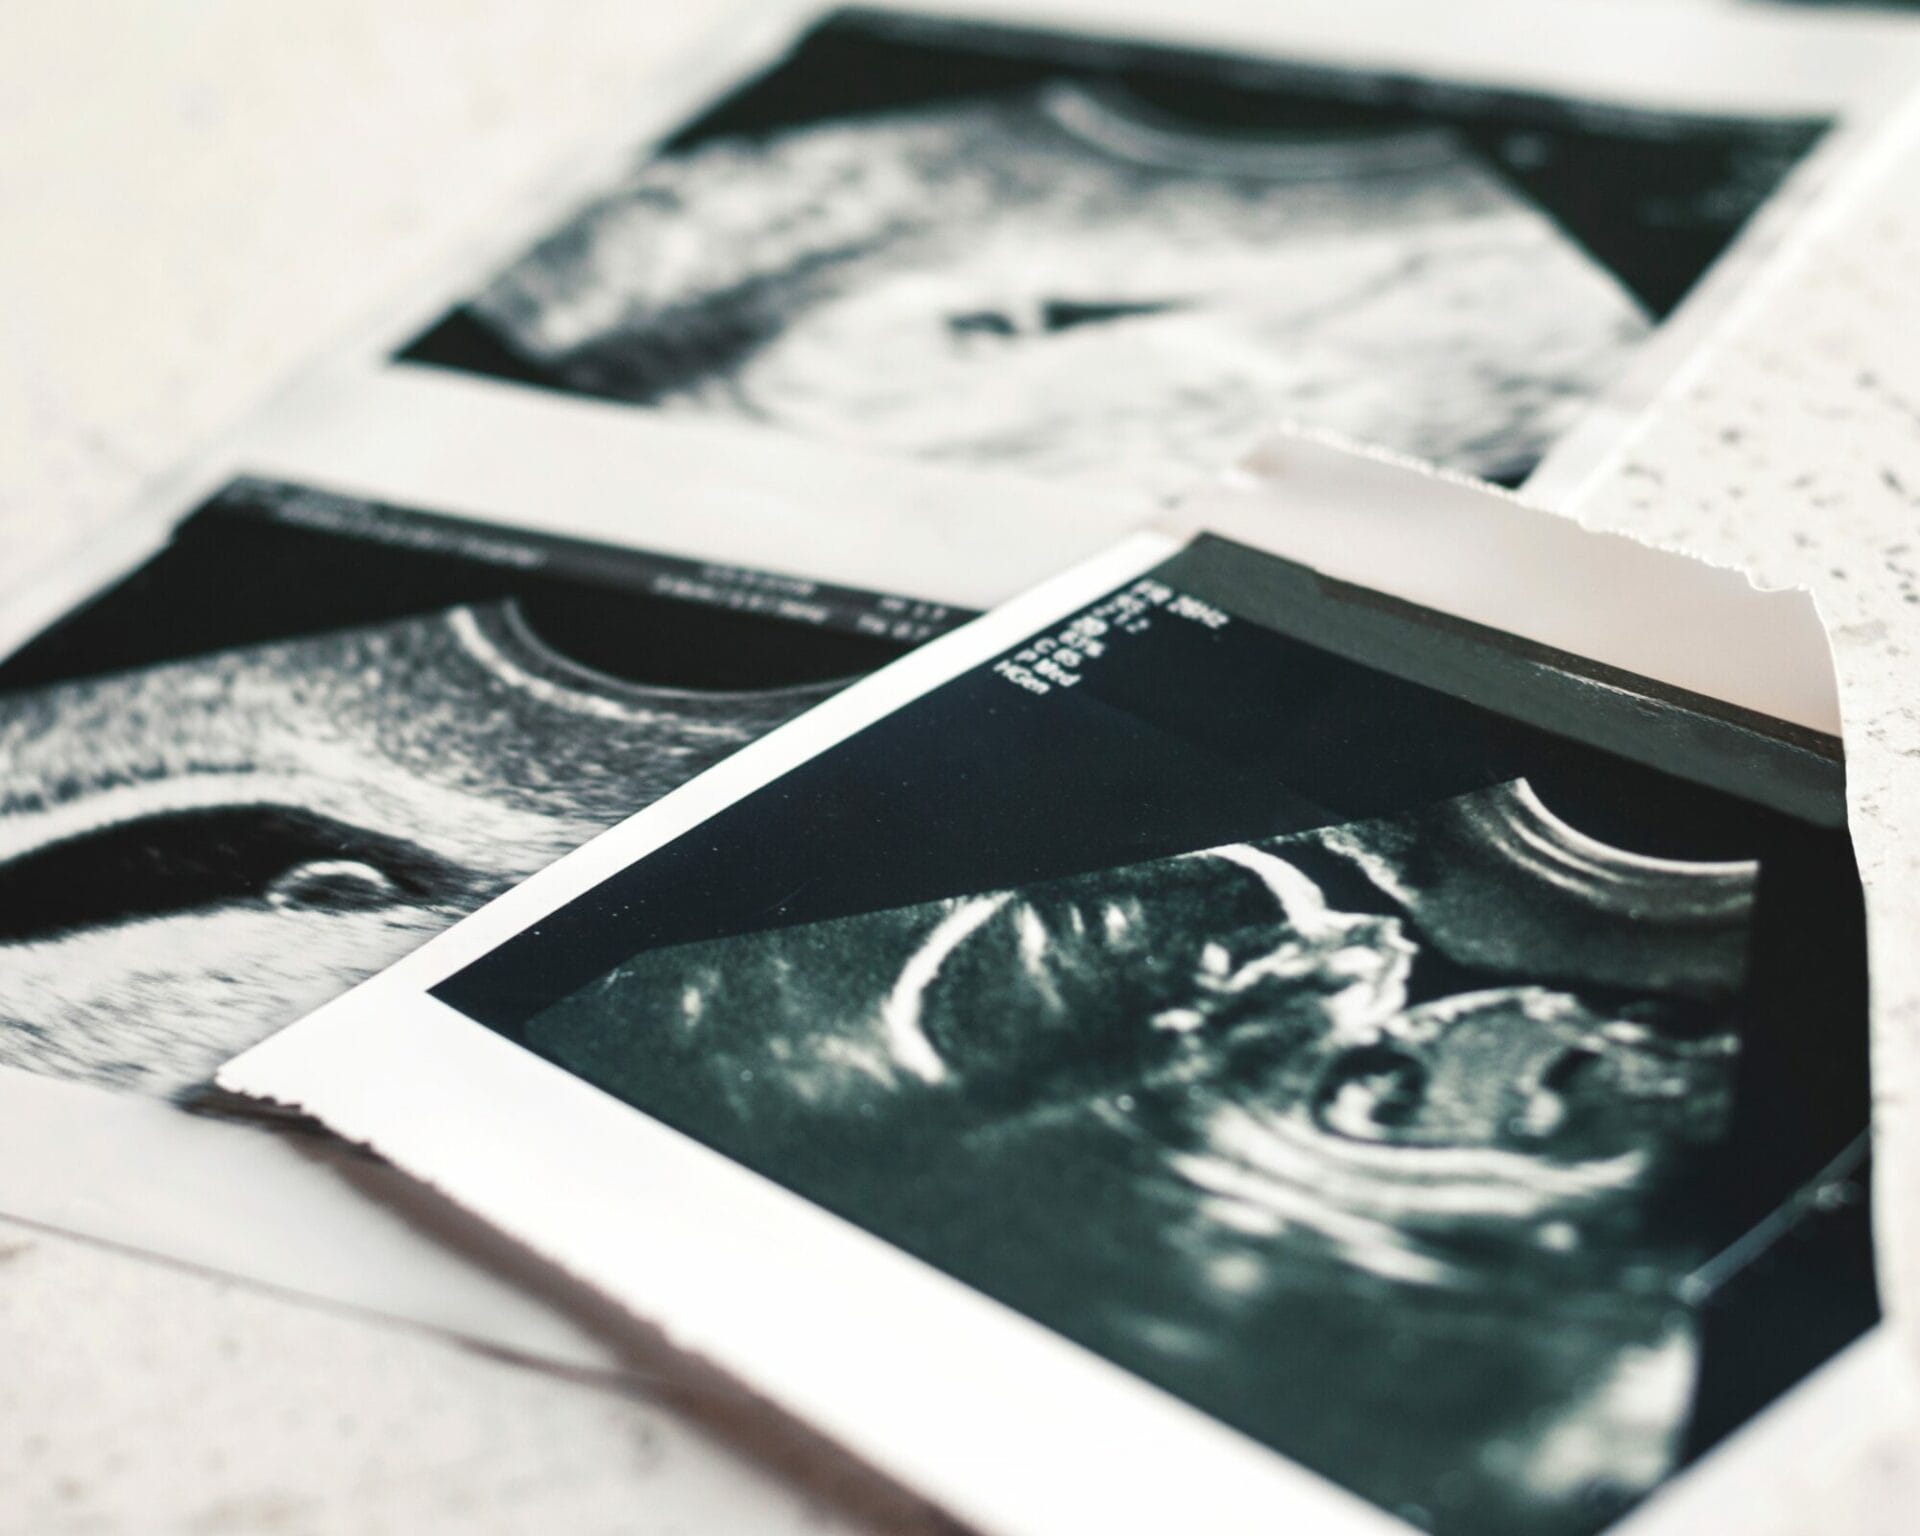

فحص الموجات الصوتية في الأسبوع السابع

عند الوصول إلى الأسبوع السابع يصبح بإمكانك إجراء فحص بالموجات فوق الصوتية، ومن خلال تلك الخطوة يستطيع الطبيب المختص من تسجيل القياسات المختلفة للطفل ومدي تطوره.

على الرغم من أن الطفل قد يبدو صغير جداً بحيث لا يمكن رصده في فحص الموجات فوق الصوتية، إلا أنه ينتج حوالي مائة خلية دماغية في الدقيقة الواحدة.

وإذا كنتي تحملين تؤام فيعرض كيسين للحمل، ومن خلال التحاليل سيعرف الطبيب كم عدد الأجنة الموجودة في الرحم خلال هذا الوقت.